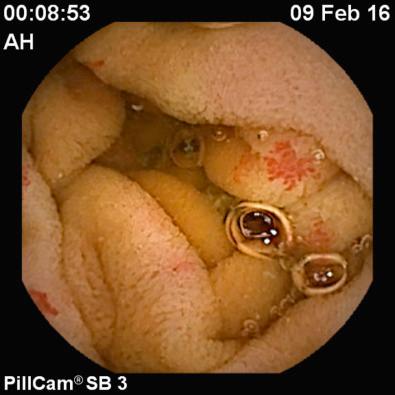

VCE allows complete evaluation of the small bowel (from the duodenum to the ileocecal valve) in 79% to 90% of patients, with a reported diagnostic yield of 38% to 83% in patients with suspected small bowel bleeding ( Figs. 17.1 and 17.2 ; ). The main utility of VCE lies in its high positive (94%-97%) and negative (83%-100%) predictive values in the evaluation of GI bleeding. Findings at VCE leading to endoscopic or surgical intervention or a change in medical management have been reported in 37% to 87% of patients ( Figs. 17.3 to 17.10 ; to ). In addition, 50% to 66% of patients have been reported to remain transfusion free without recurrent bleeding at follow-up after VCE-directed interventions. In patients who have had a negative VCE study, rebleeding occurs in 6% to 27%.

FIG 17.2, Angioectasia seen at video capsule endoscopy (VCE).